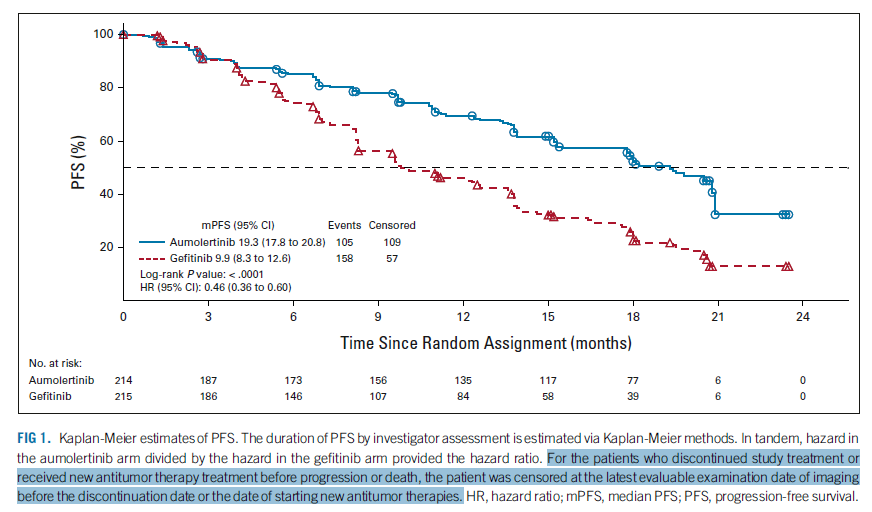

еңЁAENEASе’ҢFURLONGдёӯ����пјҢе…ідәҺеёҢжңӣеүҚжҺҘеҸ—NACTзҡ„жӮЈиҖ…����пјҢеңЁдё»иҰҒеү–жһҗдёӯеқҮе°ҶPFSеҲ еӨұеҲ°жңҖе…ҲNACTеүҚзҡ„жң«ж¬ЎеҪұеғҸеӯҰжЈҖжҹҘж—ҘжңҹпјҲеӣҫ8пјү��гҖӮ

FLAURAдёӯеҲҷе°ҶPFSз•ҢиҜҙдёәйҡҸжңәеҢ–жңҖе…ҲиҮіиӮҝзҳӨе®ўи§ӮеёҢжңӣжҲ–ж®’е‘Ҫд№Ӣй—ҙзҡ„ж—¶й—ҙ����пјҢж— и®әжӮЈиҖ…жҳҜеҗҰйҳ»жӯўжІ»з–—жҲ–еңЁеёҢжңӣеүҚжҺҘеҸ—NACT����пјҢеҚіеҝҪи§ҶNACT并继з»ӯдҪҝз”ЁNACTеҗҺзҡ„еҪұеғҸеӯҰж•°жҚ®пјҲеӣҫ9)

еҮӯиҜҒICH E9пјҲR1пјү[18]����пјҢжӮЈиҖ…еёҢжңӣеүҚжҺҘеҸ—NACTеұһдәҺдјҙеҸ‘дәӢеҠЎзҡ„дёҖз§Қ����пјҢеҸҜдҪҝз”Ёз–—жі•жҲҳз•ҘжҲ–и®ҫжғіжҲҳз•ҘжқҘи§ЈеҶіпјҡз–—жі•жҲҳз•ҘдёӢдјҙеҸ‘дәӢеҠЎзҡ„зҲҶеҸ‘дёҺз•ҢиҜҙжІ»з–—ж•Ҳеә”ж— е…і����пјҢеҚіж— и®әжҳҜеҗҰзҲҶеҸ‘дјҙеҸ‘дәӢеҠЎ����пјҢеқҮдјҡдҪҝз”Ёзӣёе…іеҸҳйҮҸзҡ„еҖј����пјҢFLAURA继з»ӯдҪҝз”ЁNACTеҗҺзҡ„еҪұеғҸеӯҰж•°жҚ®����пјҢеҚідёәз–—жі•жҲҳз•Ҙ��пјӣи®ҫжғіжҲҳз•ҘеҲҷи®ҫжғідёҖз§ҚжІЎжңүзҲҶеҸ‘дјҙеҸ‘дәӢеҠЎзҡ„жғ…жҷҜ����пјҢдҪ“зҺ°дёҙеәҠй—®йўҳзҡ„еҸҳйҮҸеҖјжҳҜеңЁжүҖеҒҮи®ҫзҡ„жғ…жҷҜдёӢжҺҘзәізҡ„еҸҳйҮҸеҖј����пјҢAENEASе’ҢFURLONGдёӯе°ҶNACTеҗҺзҡ„еҪұеғҸеӯҰж•°жҚ®дҪңеҲ еӨұеӨ„зҪ®жғ©зҪҡ����пјҢеҚідёәи®ҫжғіжҲҳз•Ҙ��гҖӮ